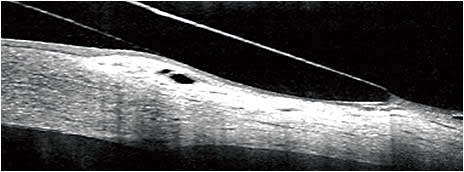

The bulbar conjunctival tissue is movable, malleable, and compressible. Even with a scleral LZ that is optimally aligned, some conjunctival compression can typically be seen following lens removal using optical coherence tomography (OCT) or a biomicroscope. Haptic compression of the conjunctiva and its superficial vasculature have been observed for many years in clinical practice and was used to determine which regions of the LZ required modifications to improve the fit. A more recent conjunctival phenomenon that appears to be unique to modern SLs is conjunctival prolapse.

Conjunctival prolapse (aka conjunctival “hooding,” “chalasis,” “inlapse,” “billowing,” “entrapment,” and “tenting”) refers to the anterior projection of conjunctival tissue beneath the periphery of a SL, sandwiched between the limbus and the innermost aspect of the LZ (Figure 4).30 The conjunctival tissue may be displaced over the limbus and peripheral cornea, but typically returns to its normal position following lens removal.